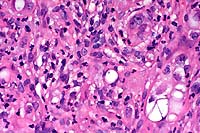

- Case 15-4. Liver. Severe focal to coalescing necrosis

is associated with inflammatory cell infiltration and syncytial

giant cells.

40x

obj

- Case 15-4. Liver. Areas of hepatocellular necrosis

are replaced by necrotic cellular debris, hemorrhage, neutrophils

and occasional clusters of nuclei (hepatocyte syncytium). An

adjacent hepatic vein contains endothelial cell hypertrophy and

hyperplasia.